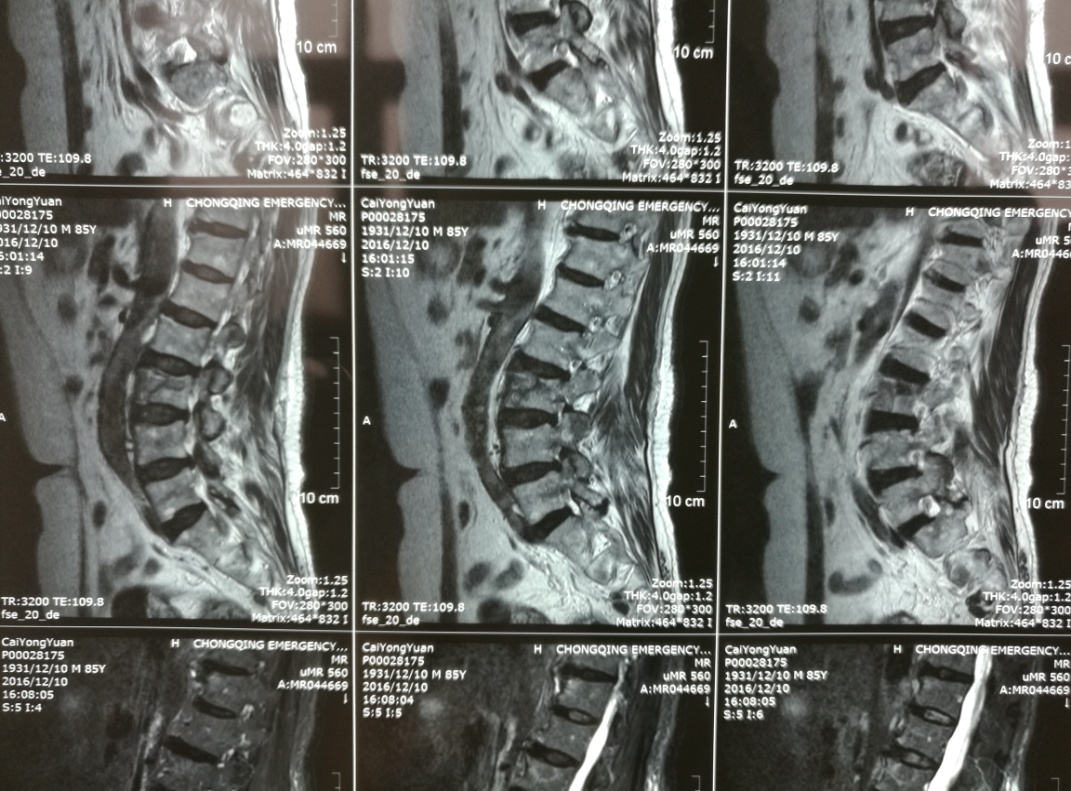

市职防院成功开展自主经皮椎体(后凸)成形术(PKP、PVP)

我院骨科于近日成功开阵多例经皮椎体后凸成形术(PKP)及经皮椎体成形术(PVP),数名患者均恢复良好。这是我院骨科在积极开拓新业务,开展新技术,更好地为广大患者服务的又一硕果。 骨质疏...